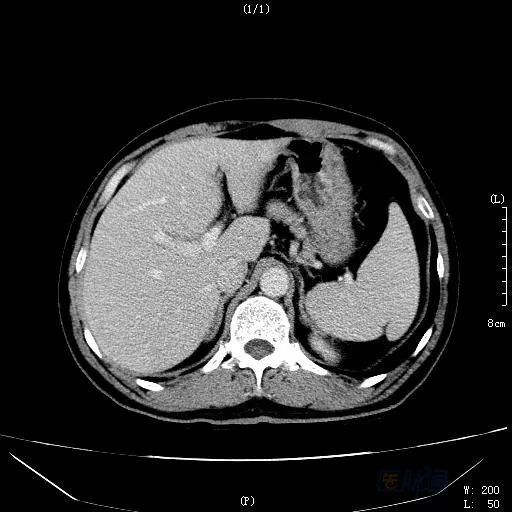

之后,患者电话笔者申请会诊,赴约。仔细阅读病例病史,发现患者并无既往肝病史,乙肝两对半、丙肝等检查无阳性结果,无饮酒等嗜好;患者虽似乎有肝衰竭的症状表现,但凝血指标基本正常,经过保肝治疗,病情也明显好转。阅读CT、MRI发现:肝左内叶见一高密度影,但三期无明显变化,肝脏体积偏大,呈不均质改变,MRI提示非脂肪病变,肝静脉显示不清。此时,笔者心里基本有了答案,随后追问患者病史,立即带回我院。患者经治疗三个月后,肝脏密度逐渐正常,原来的占位病灶消失(见图3)。

图2 治疗一个月后CT门静脉期扫描

图3 治疗三个月后CT延迟期扫描

HSOS的CT平扫显示为肝实质密度不均匀减低,腹水、肝脏体积增大等表现,此与肝脏淤血及肝细胞变性、坏死相关。由于窦后性门脉高压造成门脉期强化峰值减低或延迟;肝脏淤血及肝细胞变性、坏死则造成无或低灌注区域;另外,由于尚存相对正常的肝脏组织,而这类组织的门静脉灌注相对正常,便产生了正常肝组织与受损组织之间的强化差异;肝脏显示特征性的斑片样、地图样强化和低灌注区。延迟扫描:由于门脉强化峰值延迟、门静脉血流灌注增加,出现低密度区域减少和增强区域增加,肝脏密度趋于一致,而如果延迟后仍为低灌注的区域,则提示这部分的肝脏组织坏死严重。